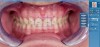

Fig 11. Radiograph of healed implant site No. 8 at 3 months.

Figure 11

Fig 12. Clinical presentation of healed soft tissue and final custom abutment No. 8 placed on the day of the implant surgery 3 months prior.

Figure 12

Plugging into digital workflows provides opportunities to integrate CAD/CAM technologies at every step of the treatment process for dental implants. In another example, a patient presented with a failing tooth No. 8 (Figure 6 and Figure 7). After discussing treatment options, the patient chose to forgo any treatment to address tooth and soft-tissue asymmetries and wanted to proceed with a dental implant-supported restoration without additional treatment. After integrated 3-dimensional planning, the tooth was extracted, and then an implant and the final custom CAD/CAM abutment (titanium base with zirconia supra-structure) were placed with a provisional restoration in the same visit (Figure 8 and Figure 9). Soft-tissue grafting was also done at the same visit to address the deficient buccal tissue height on No. 8 (Figure 10). At 3 months, the patient presented for the final restoration, with excellent healing around the implant (Figure 11) and soft-tissue healing guided by the custom abutment (Figure 12).